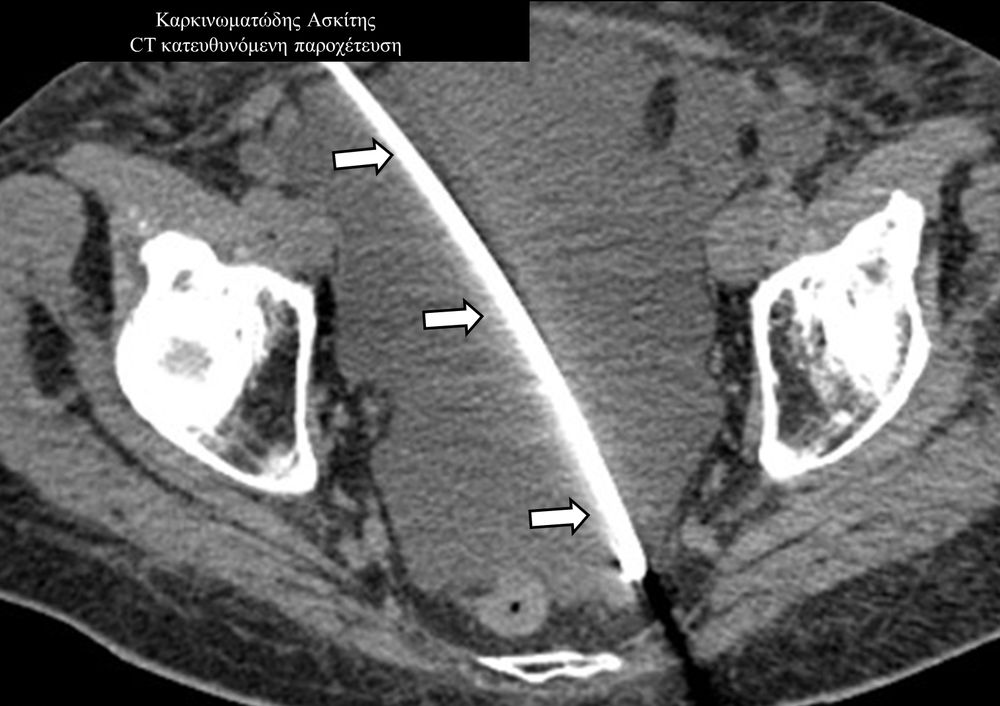

Οι απεικονιστικά καθοδηγούμενες διαδερμικές παροχετεύσεις είναι ελάχιστα επεμβατικές μέθοδοι εξωτερικής παροχέτευσης συμπτωματικών συλλογών, όπως ασκιτικές-καρκινικές-μετεγχειρητικές συλλογές, αποστήματα, πλευριτικές συλλογές-εμπυήματα.

Η διαδερμική παροχέτευση συλλογών συμβάλλει σημαντικά στην καλύτερη ποιότητα ζωής του ογκολογικού ασθενούς, αντιμετωπίζει τις οξείες τοξικές επιδράσεις στον οργανισμό που μπορούν να αποβούν θανατηφόρες, αλλά και επιτρέπει την απρόσκοπτη συνέχιση της θεραπείας του.

Η παρέμβαση διενεργείται υπό την καθοδήγηση αξονικού τομογράφου ή υπερήχων ή και με συνδυασμό τους. Ο επεμβατικός ακτινολόγος αρχικά αναισθητοποιεί την ανατομική περιοχή ενδιαφέροντος με τη χρήση τοπικής αναισθησίας και παρακεντεί την συλλογή διαδερμικά με λεπτή βελόνη. Στη συνέχεια μέσω ομοαξονικών συστημάτων συρμάτων-καθετήρων-διαστολέωντοποθετείται διαδερμικός καθετήρας τύπου pig-tail εντός της συλλογής, ο οποίος συνδέεται με εξωτερική παροχέτευση.